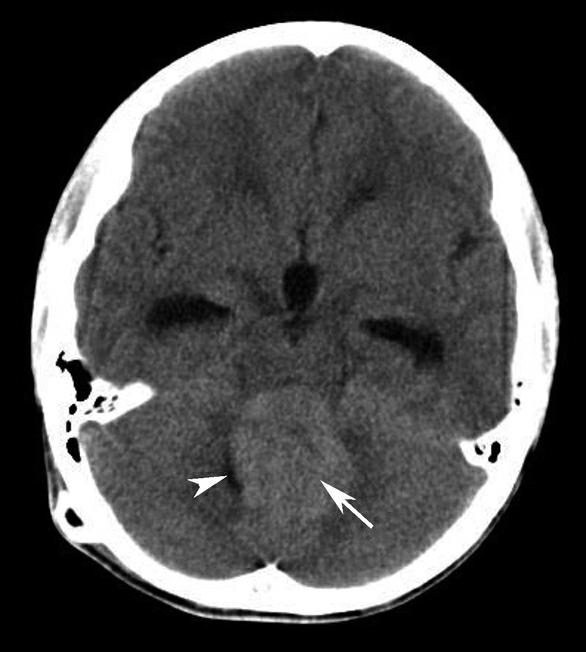

蝶鞍两侧为海绵窦,其内包含颈内动脉及第Ⅲ~Ⅵ对脑神经。海绵窦的密度升高或体积增大常提示病变存在。海绵窦外侧为颞叶,两者之间隔以海绵窦外侧壁。鞍背后方为桥前池及其后方的脑桥,桥前池内可见基底动脉断面,呈圆形稍高密度影。层面中部两侧为颞骨乳突部,其内气化的骨性腔隙为乳突气房。脑桥后方为第四脑室,呈半圆形或新月形,小脑半球的病变(如肿瘤、炎症、出血等)常压迫第四脑室,导致其变形甚至闭塞(图1-2-13)。两侧小脑半球间为小脑蚓部。小脑半球与颞骨乳突部间可见乙状窦。小脑蚓部后方为直窦与上矢状窦汇入窦汇处,窦汇两侧为横窦。静脉窦血栓时可见上述静脉窦增宽、密度明显升高(图1-2-14)。

图1-2-13 第四脑室变形(小脑转移瘤)

A.第四脑室受压变形右移(白箭),提示左侧小脑半球病变;B.左侧小脑半球环形强化结节(黑箭),为瘤体,其周围伴有低密度水肿区